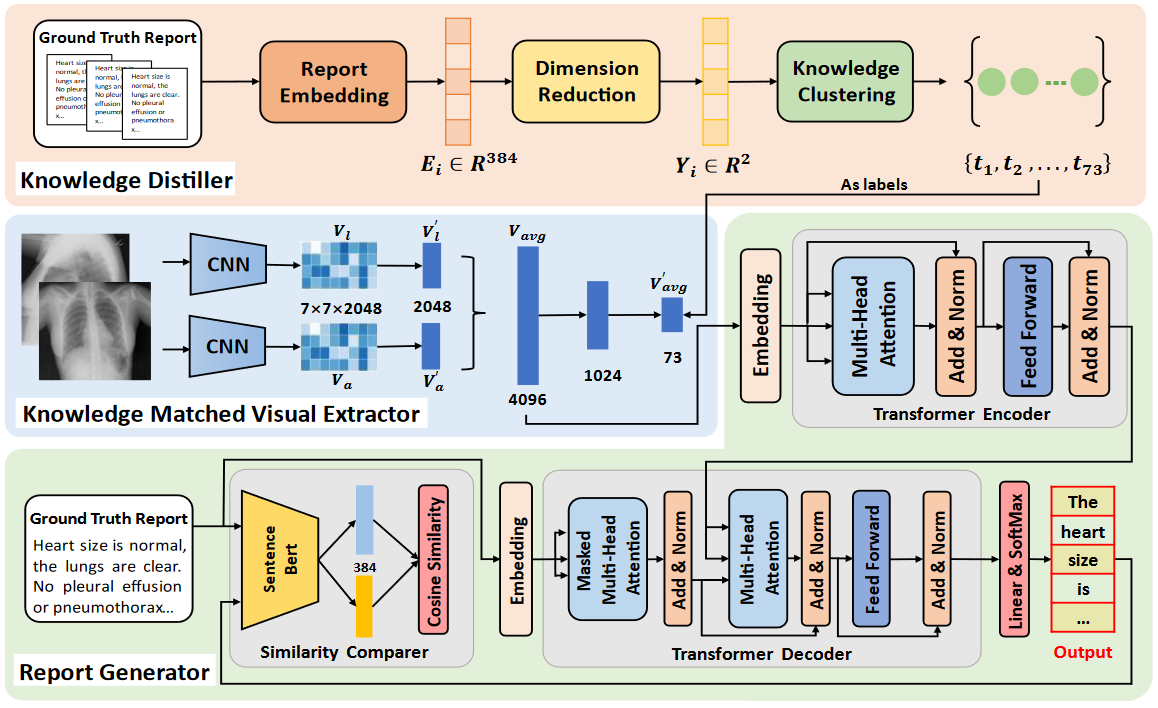

Computerized Medical Imaging and Graphics (CMIG), 2022.

Zhiqiang Tan, Jun Li, Huiren Tao, Shibo Li, Ying Hu.

[paper]